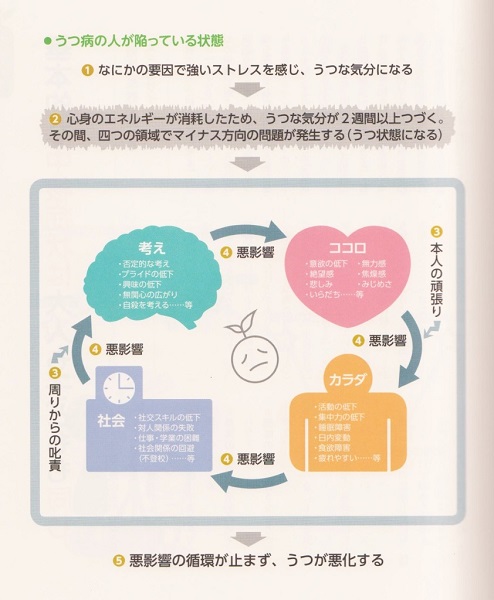

うつ病の場合は、何らかの要因で強いストレスを感じてうつな状態となり、そのうつ状態が2週間以上続き、同時に生活においてもマイナス的な態度や言動が増え、元の状態に戻らない場合うつ病の可能性が高いといえます。

特にこ「うつ病」の状態に陥ってしまっている場合。

認知面や行動面で問題が生じてきます。

<認知面の問題>

・考え

否定的な考え、興味の低下、無関心、自尊心の低下、自殺願望など

・ココロ

意識の低下、無力感、絶望感、焦燥感、悲しみ、みじめさ、いらだちなど

<行動面>

・カラダ

やる気の低下、集中力の低下、睡眠障害、食欲障害、メタボ、日内変動、慢性疲労など

・社会

社交性の低下、対人関係の失敗、学業困難、不登校など

うつ状態になる場合、この悪影響の循環が止まらずどんどんうつが悪化していきます。